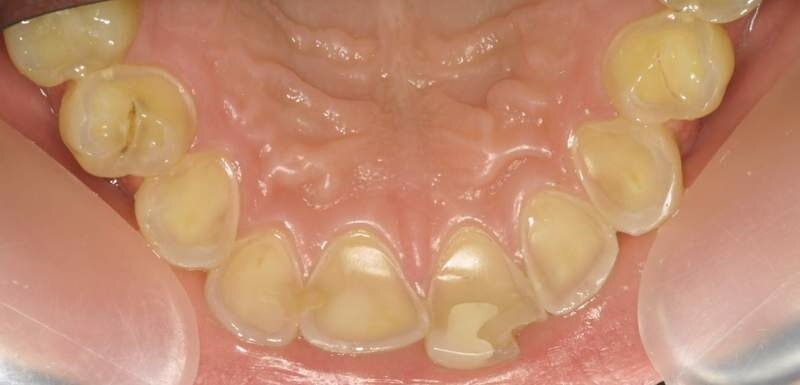

What kind of post-developmental loss of tooth structure is this?

Erosion